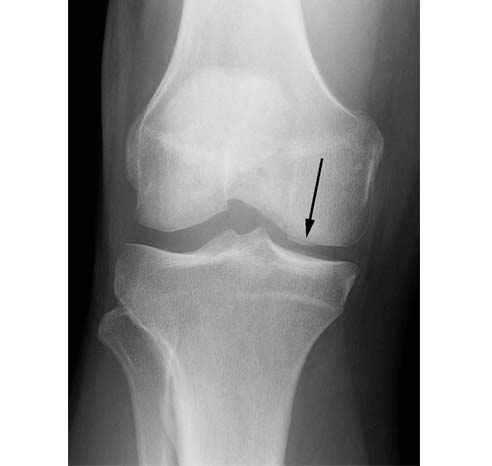

The patient is a 40 year old male with a work related injury to his knee when lifting a 90 lbs suitcase. He had complaints of pain on the inside (medial aspect) of his knee.

6.On the postoperative xray, the graft can be seen in the medial femoral condyle (black arrow).